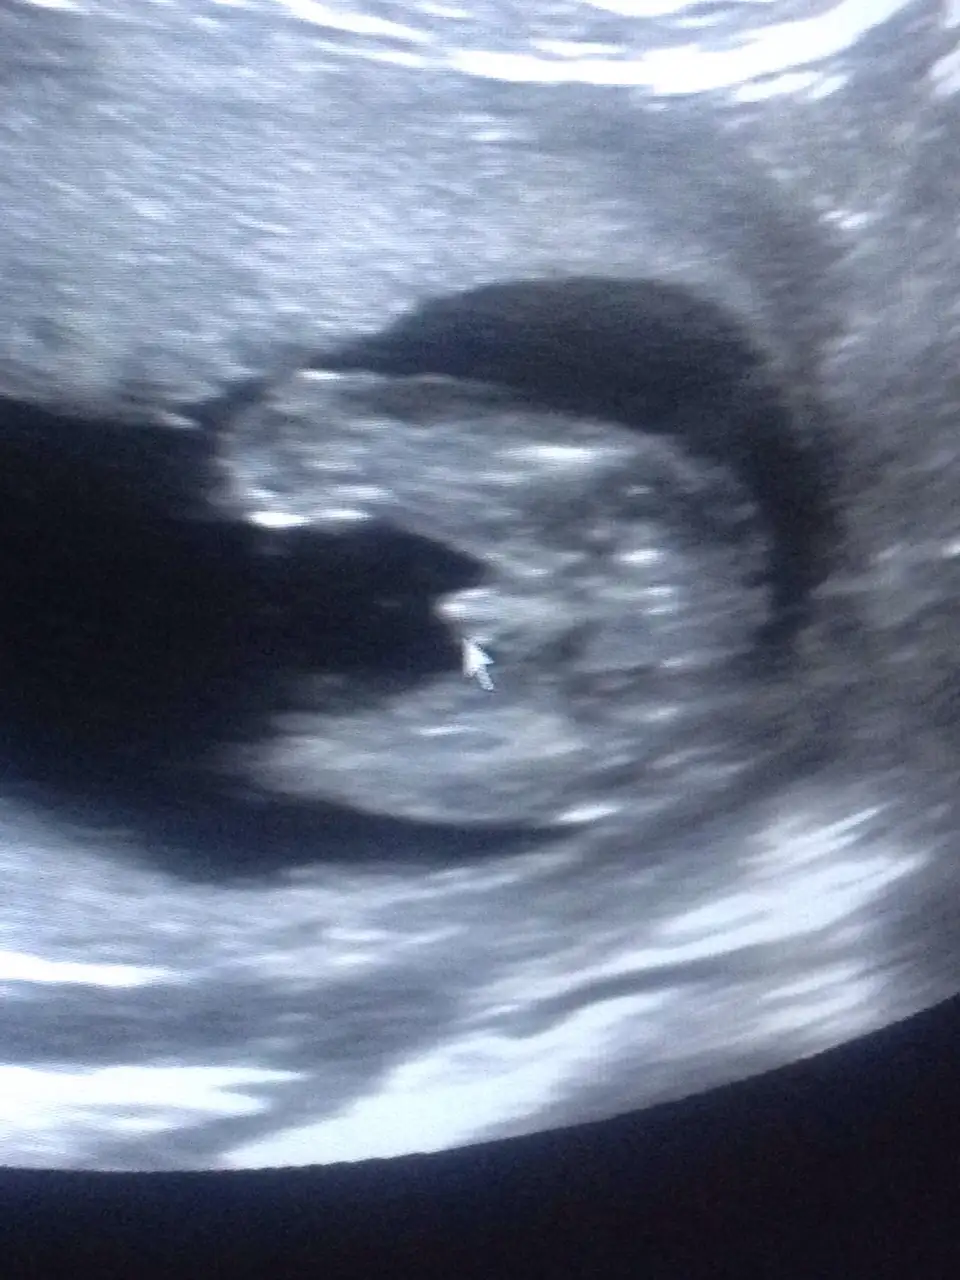

Canim bugün tekrar kontrole gitti gecen hic yorum yapmamisti bugunde bacaklarini acmadigini ama %60 koza benziyor dedi kafayi yedirtecek bana 15 haftalıkken doktor tesislerine pipisine varana kadar gösterdi ama bu kiza benziyor değip gecistiriyorSirti donuk ama uccizgi goruyorum kiz galiba